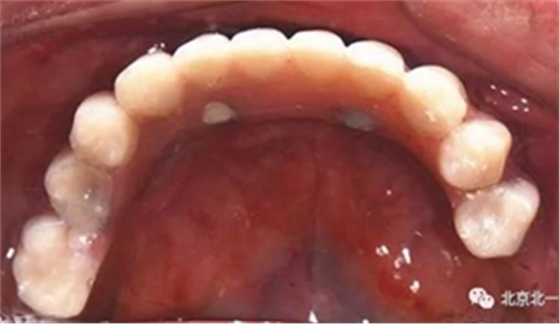

圖十八:口內(nèi)試戴鈦支架

圖十九:永久修復(fù)完成